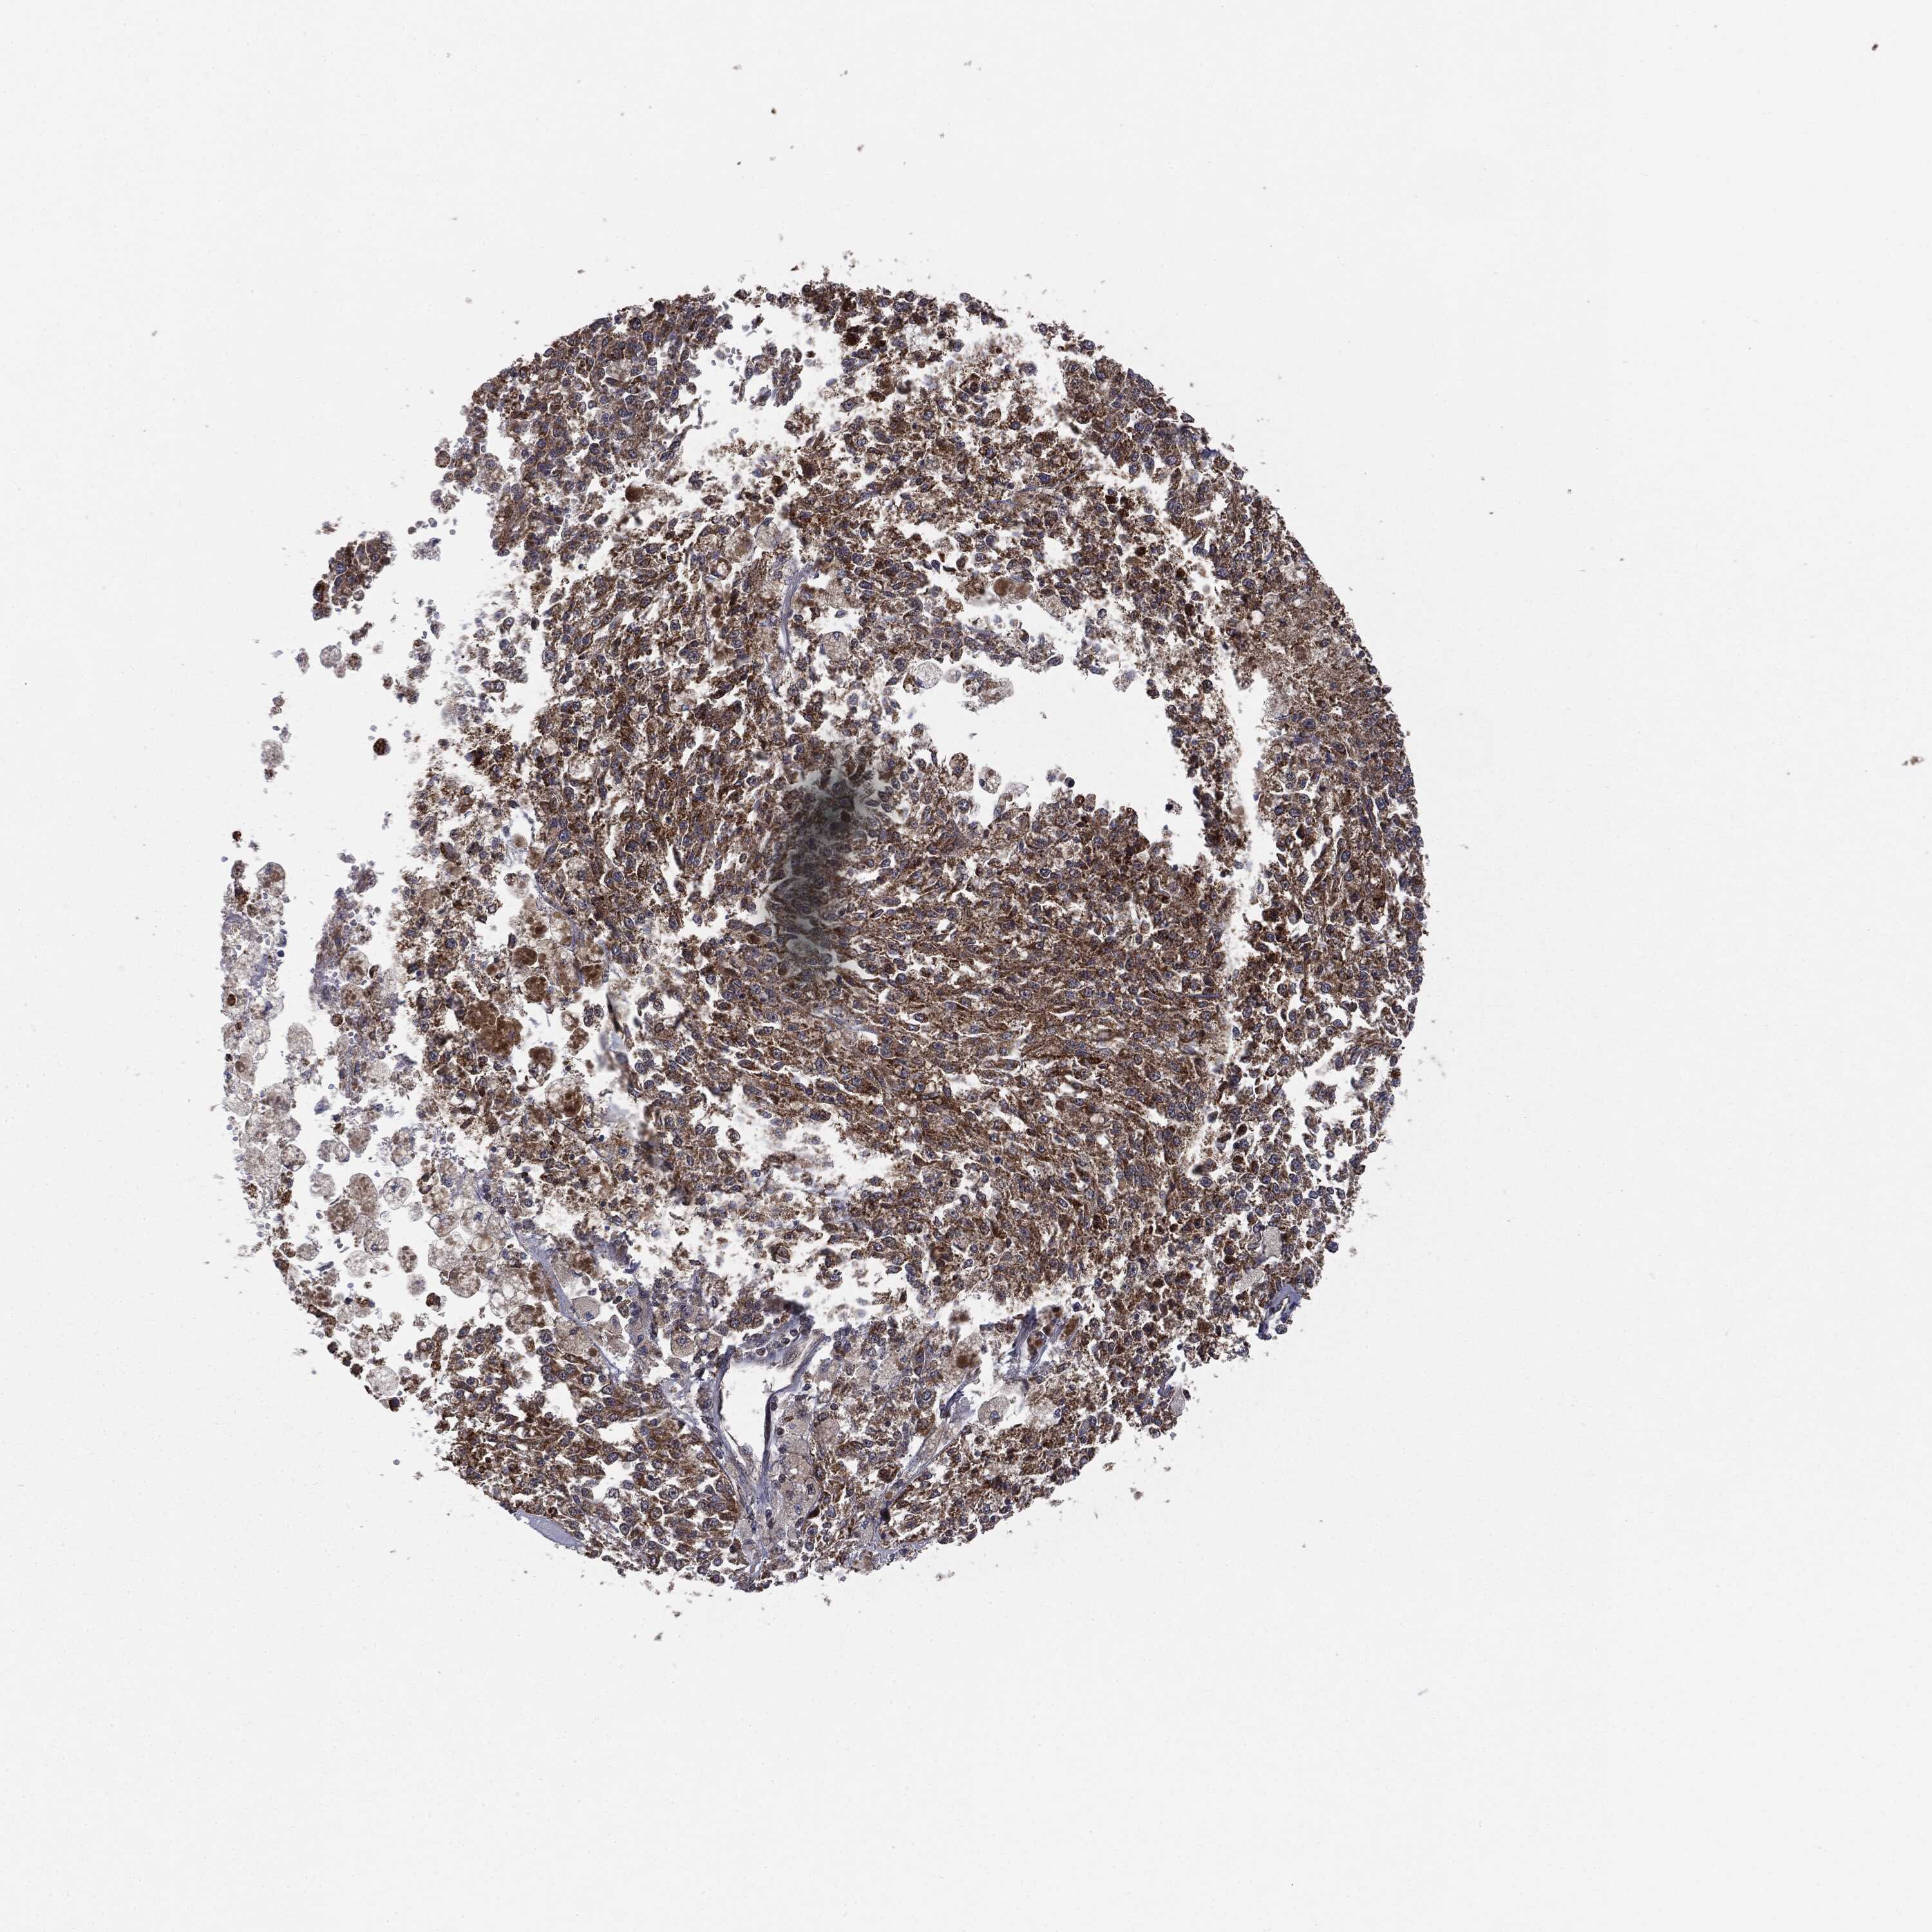

MELANOMA - Protein expressioni

A mouse-over function shows sample information and annotation data. Click on an image to view it in a full screen mode. Samples can be filtered based on level of antibody staining by selecting one or several of the following categories: high, medium, low and not detected. The assay and annotation is described here.

Note that samples used for immunohistochemistry by the Human Protein Atlas do not correspond to samples in the TCGA dataset.

Antibody stainingi

Antibody staining in the annotated cell types in the current human tissue is reported as not detected, low, medium, or high, based on conventional immunohistochemistry profiling in selected tissues. This score is based on the combination of the staining intensity and fraction of stained cells.

Each image is clickable and will lead to virtual microscopy that enables deeper exploration of all samples and also displays staining intensity scores, fraction scores and subcellular localization as well as patient and tissue information for each sample.

Malignant melanoma, NOS

Malignant melanoma, Metastatic site